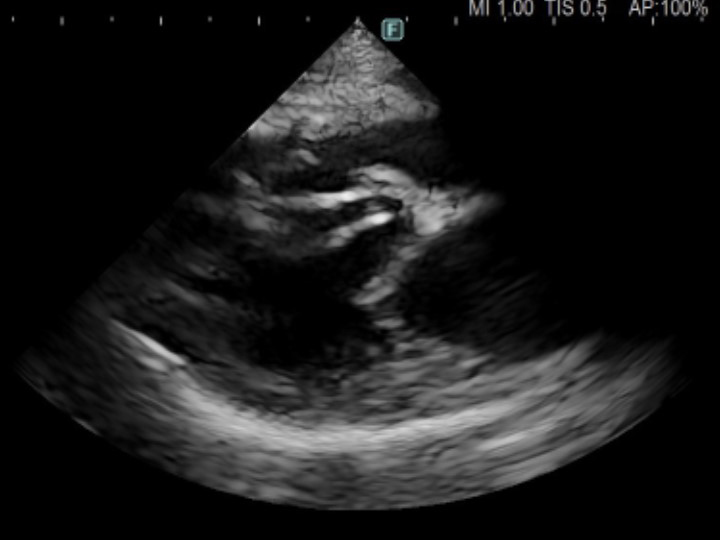

術後の心臓のエコー画像。心嚢水による圧排が解除されて正常な動きが可能になった。